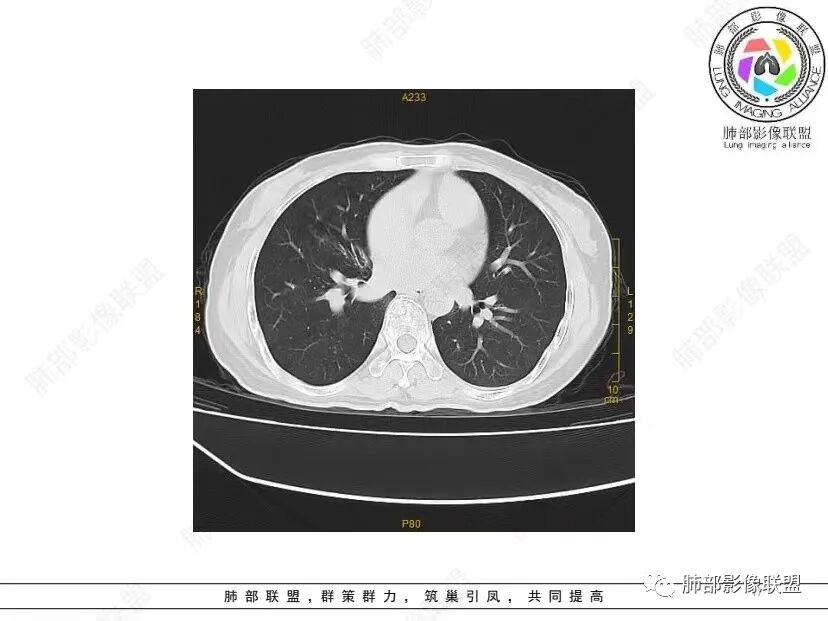

中年女性,否认肿瘤病史,双肺多发气囊,中下肺相对多发,考虑LIP,鉴别BHD综合征。

秦化君: 晨读 双肺不均匀散在多发囊状影,大小不等,部分囊形态欠规整,壁薄均匀,部分囊胸膜下平行。双肺少许斑片状磨玻璃影,边缘模糊。考虑BHD综合征。鉴别PCP,LIP。

红日初升: 中年女性,双肺多发气囊,背景干净,大小不一,下肺韧带旁较大,考虑BHD,鉴别LIP、LAM

玫: 晨读:女,49岁,双肺散在多发囊性病灶影,薄壁,部分层面病灶形态欠规整,右肺下叶少许磨玻璃影,边缘模糊,考虑LIP,鉴别BHD。

宇宙: 中年女性,两肺多发大小不等薄壁囊状影,两肺纵膈胸膜下分布明显,考虑BHD,鉴别LAM

放射线 (王秀仙): 双肺多发囊状影,大小不等,部分囊壁呈磨玻璃样,另双肺见斑片状磨玻璃影,边缘模糊。女性,考虑LIP,鉴别BHD

段建民: 双肺多发囊状影,多成圆形或三角形,囊壁薄且均匀,正常肺野内透过度尚可。双肺多发囊状影的鉴别,中心肺气肿,间隔旁肺气肿,PJP,支气管扩张,囊肿,支气管肺发育异常;LAM LIP PLCH BHD;囊腔腺癌,转移瘤,血播金葡菌……

本病例首先考虑BHD。

小飞: 晨读,中年女性,病史保密,两肺散在薄壁囊腔,肺底较多,部分较大,双肺少许磨玻璃密度影,考虑LIP

良孑: 两肺多发含气囊腔,大小不等,囊周见血管伴行,首选BHD,建议查双肾情况,鉴别Lam

这个病例目前影像特点,多囊,囊主要位于下肺,胸膜下及小叶核心为主

伴随少许索条,而且这些病灶与囊不一定有相关性

囊的分布,PLCH基本可以排除

囊壁薄且均匀,光滑,形态规则,基本除外恶性

单纯囊,无斑片及其他实性病灶,感染不支持,可能的是:LAM、BHD、LIP

从囊的分布、大小,BHD可能性可能大一些,但是LIP、LAM都可以这样表现,具体诊断应该是这三种之一,影像缩小到这里我觉得就差不多了,结合临床考虑就行,不支持靠影像强下结论。